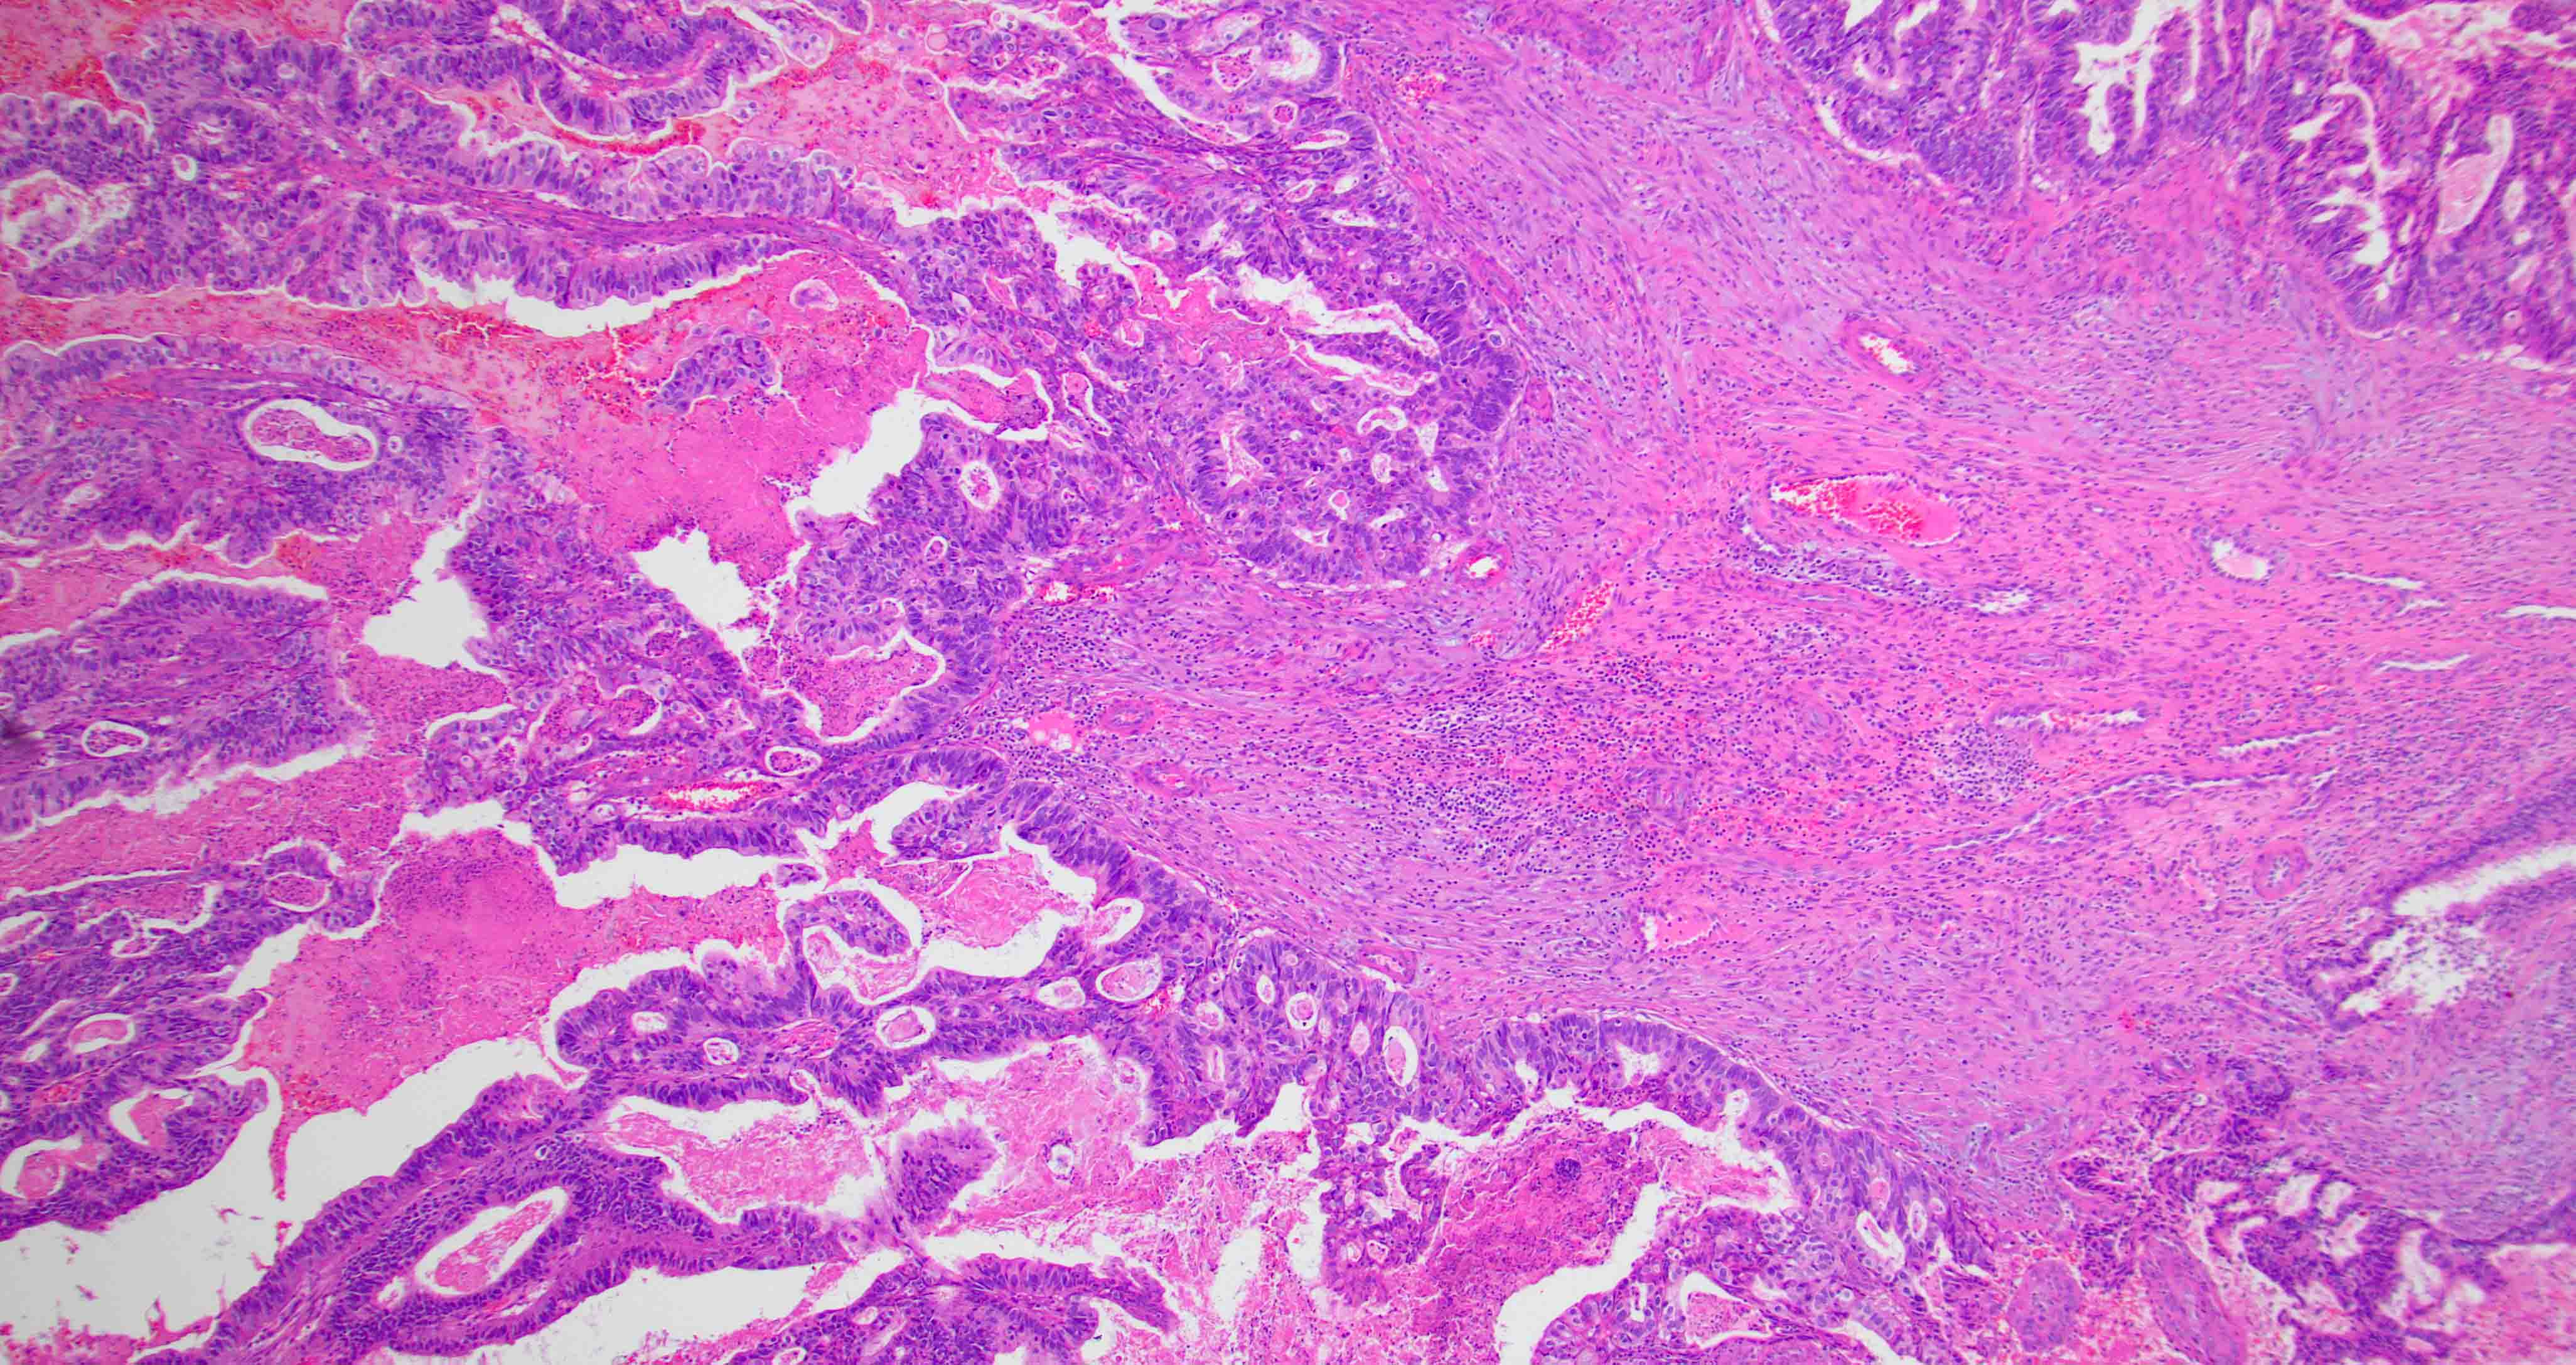

Microscopic (histologic) images

Contributed by Diana Bell, M.D.

Intestinal adenocarcinoma (ITAC)

Nonintestinal adenocarcinoma (non-ITAC)

- ITAC displays glandular, tubular and trabecular architecture and few papillae and resembles a conventional colorectal adenocarcinoma

- Exclusion of metastasis from primary gastrointestinal tract tumor is required